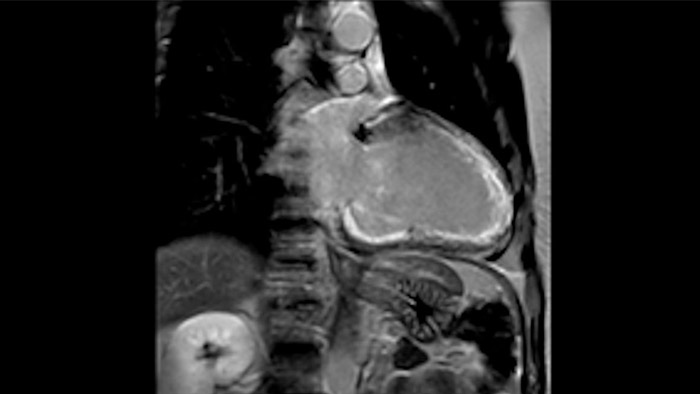

La utilidad diagnóstica y pronóstica de la RM cardíaca está aumentando. Evaluar la anatomía y función del corazón mediante adquisiciones cinematográficas, adquirir información sobre perfusión y viabilidad del tejido cardíaco, visualizar posibles edemas con secuencia de sangre negra, acceder e incluso cuantificar la caracterización tisular con CardiacQuant.